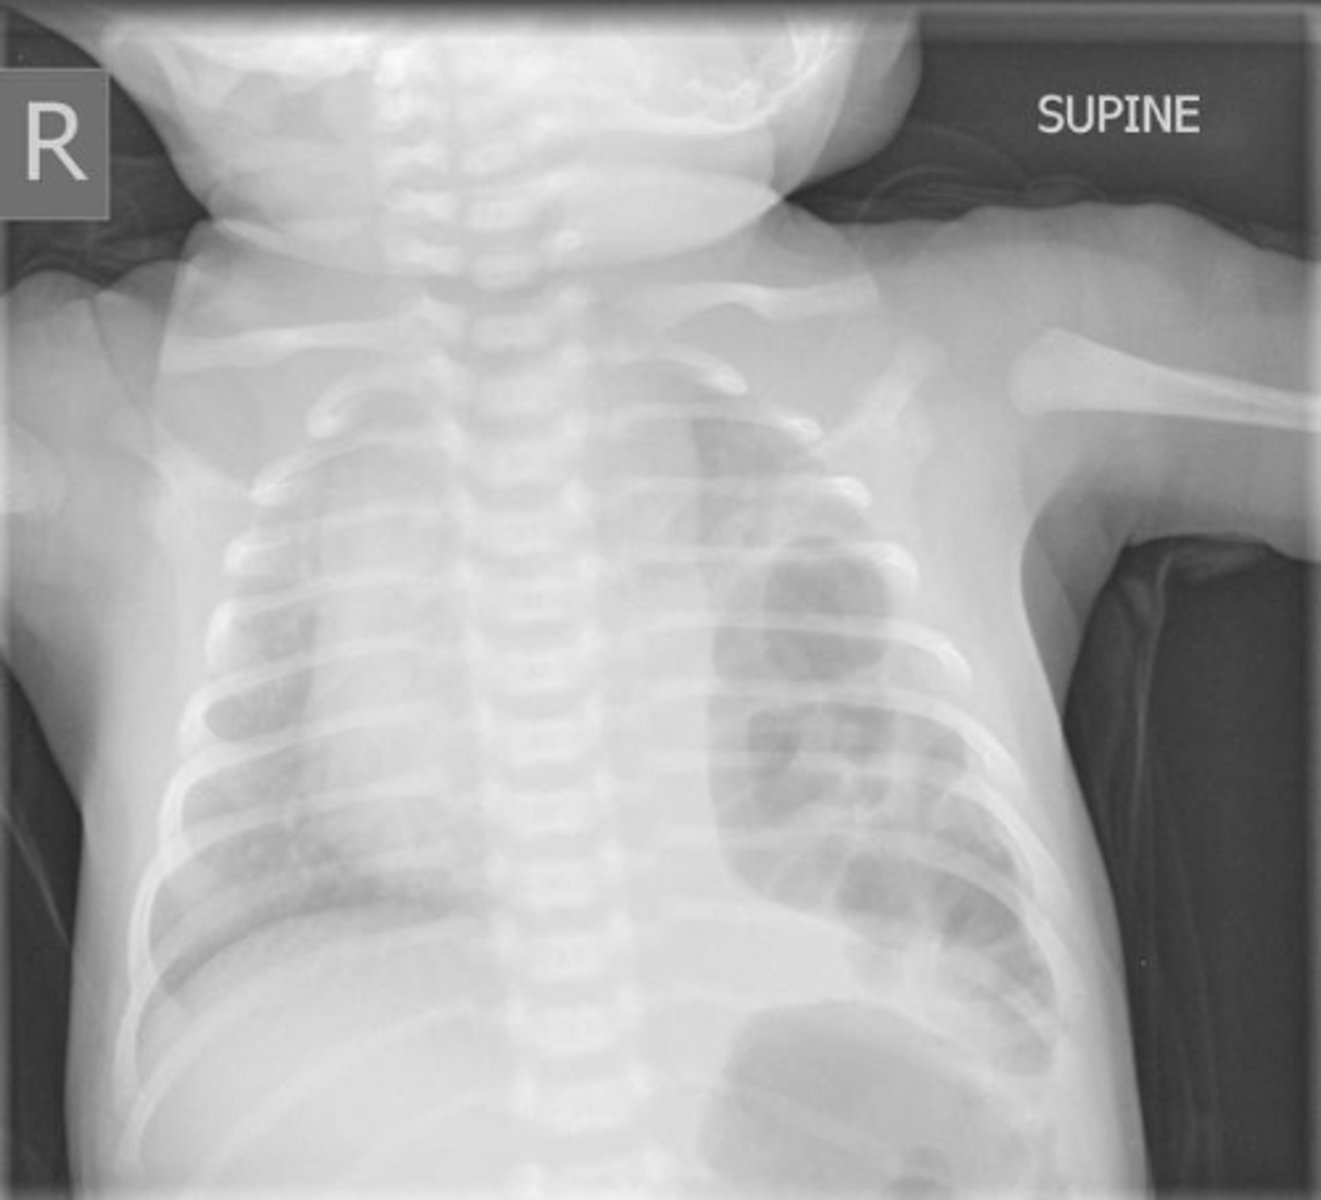

Baby is born w/ respiratory distress, scaphoid abdomen & this CXR.

• Biggest concern?

• Best treatment?

Diaphragmatic hernia

Concern: Pulmonary hypoplasia

Txt: If dx prenatally, plan delivery at @ place w/ ECMO. Let lungs mature 3-4 days then do surg